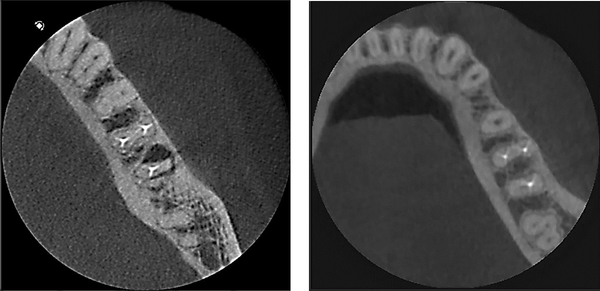

La risoluzione del sensore è invece la dimensione del più piccolo dettaglio visibile nell’immagine. Sul mercato si trovano macchine in grado di acquisire immagini con un dettaglio minimo di 120, 100, 80, 70, 68 micron. Ciò che spesso viene ignorato è che la qualità dell’immagine quasi sempre è inversamente proporzionale alla risoluzione. Quindi una sezione di CBCT con un dettaglio di 400micron è molto più “leggibile” agli occhi del medico rispetto a una sezione con dettaglio di 80micron, e questo accade perché maggiore è il dettaglio e maggiore è anche il disturbo creato nell’immagine da metalli, tessuti molli e, in generale, da tutti gli elementi anatomici che in realtà non ci interesserebbe vedere. Di conseguenza non bisogna limitarsi a consultare le brochure per vedere quale dispositivo ha la maggiore risoluzione, perché non è assolutamente detto che quel dispositivo abbia l’immagine di migliore qualità, anzi, i dispositivi che offrono risoluzioni molto elevate e, al tempo stesso, vogliono offrire un’alta qualità diagnostica, per forza di cose devono montare sensori molto sofisticati e utilizzare algoritmi di costruzione dell’immagine molto complessi; dispositivi con queste caratteristiche devono, di conseguenza, collocarsi nelle fasce di prezzo più alte. Un dispositivo a basso costo che offre alte risoluzioni è un ottimo candidato a offrire delle pessime immagini.

Nella figura due sezioni tratte da due indagini CBCT, entrambe con una risoluzione di 80micron. E’ evidente la differenza di qualità delle due immagini